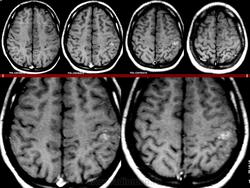

Миксоидная саркома.

1.m.slayd191.jpg2.m.slayd192.jpg3.m.slayd193.jpg4.m.slayd194.jpg5.m.slayd195.jpg6.m.slayd196.jpg7.m.slayd197.jpg8.m.slayd198.jpg9.m.slayd199.jpg10.m.slayd200.jpg11.m..slayd201.jpg12.m.slayd202.jpg13.m..slayd203.jpg